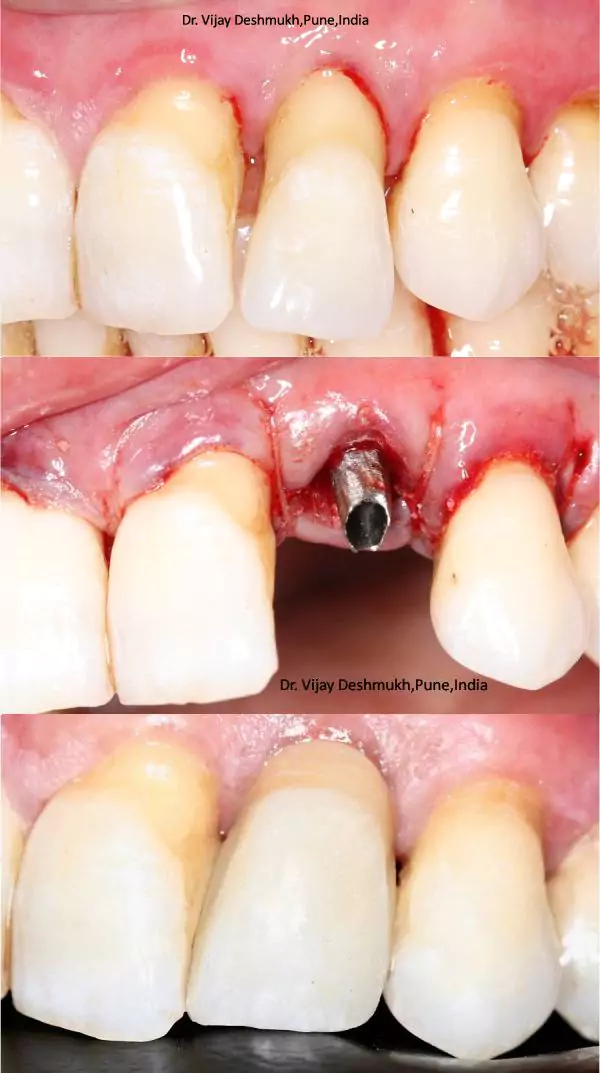

Smile Journey Highlights

Extra Image 1

Teeth extraction (if necessary) and implant placement.Temporary crowns or bridges attached for immediate function and aesthetics.